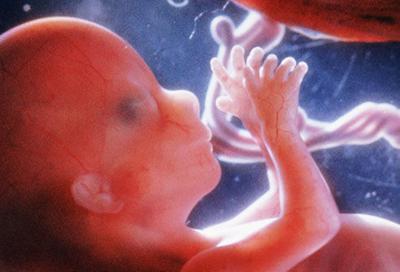

八、此时胎儿已长到四个半月,他移 动手臂,把手指放在唇边,这可以促进它对吮吸的反映。